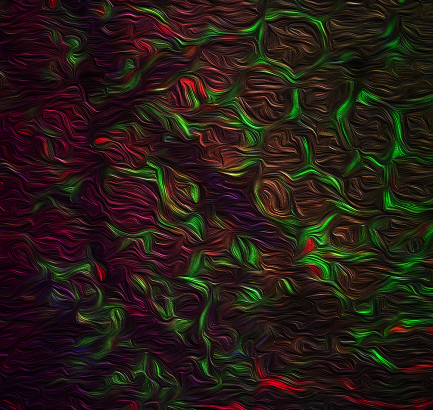

A microscopic image of the colon shows dynamic interactions between macrophages (labeled in green) and innate lymphoid cells (labeled in red). The IBD-linked protein called TL1A plays a central role in the communication between these cells and regulates colonic immunity and inflammation.